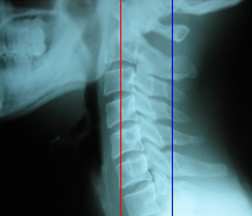

거북목 /일자목 / 목뼈의 후만 (역c자형 목)

정상적으로 인체의 중심중력선은 어깨의 중심과 귀를 동시에 통과해야 하는데 목이 전체적으로 앞으로 빠져 나가면 거북목이 형성됩니다. 이 때 정상적인 경추 만곡을 유지 할 수도 있지만 대부분 만곡이 소실되면서 일자목화 되거나 심하면 후만(뒤로 볼록한 형태) 을 형성하기도 하고 과도하게 전만(앞으로 볼록한 형태)이 되기도 합니다